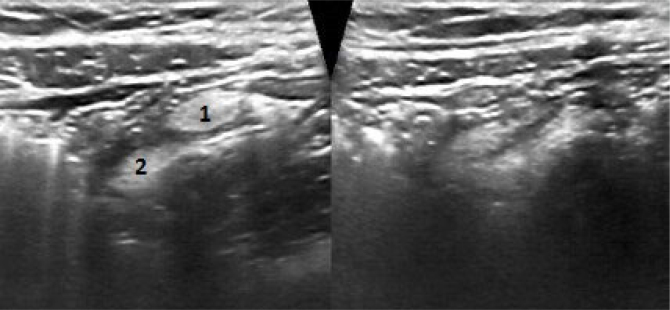

The aim of this paper is to present our experience in transabdominal ultrasonography of ileocecal valve lesions. The ileocecal valve, located in the central part of the ileocecal bowel segment, is rarely the primary site of disease processes. It is usually involved by pathologies in adjacent bowel segments. These are primarily infectious diseases such as yersiniosis, campylobacteriosis and salmonellosis. Typical location of Crohn's lesions also promotes valve involvement. The appearance of the lesions in these cases is characterized by a symmetrical submucosal thickening of the bowel involved over a longer segment. Non-malignant valvular hyperplasia is relatively commonly identified as lipomatosis, manifested by symmetrical enlargement and smooth outlines. However, valvular lipoma causing an asymmetrical hyperechoic bulge is a rare finding. ileocecal valve lipomatosis or lipoma should not be misdiagnosed as a lipoma of the cecoascending part of the colon and, the other way round, a right colonic lipoma should not be mistaken for a fatty valve. Polyps on the ileocecal valve, although sometimes detected, were not identified in our material. Adenocarcinoma, which is found in the cecum in approximately ¼ of cases, is the most common malignancy, followed by neuroendocrine tumor and, rarely, lymphoma. In three cases of malignant involvement of the ileocecal valve, we observed irregular hypoechoic thickening with complete loss of wall stratification, with the lesions causing symptoms of small bowel obstruction in two of these cases. The nearly forgotten ileocecal valve syndrome, also known as Bauhin's ileocecal valve syndrome, characterized by intermittent right iliac fossa pain, is also briefly discussed. Transabdominal ultrasound can be used as an initial diagnostic tool in some of these pathologies.

Abstract Image